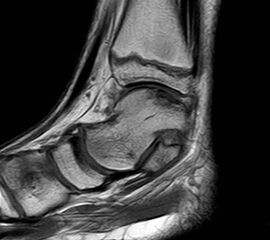

MRT

Die Kernspintomographie hat ihre Stärke in der Darstellung von Weichteilverletzungen. Insbesondere Verletzungen der Wachstumsfuge, des Periosts und der Bänder lassen sich gut visualisieren. Nachteilig ist die Untersuchungsdauer von 20-30 Minuten. Bleibt das Kind während dieser Zeit nicht ruhig liegen, kommt es zu Bewegungsartefakten, welche die Beurteilbarkeit der Bilder beeinträchtigen.